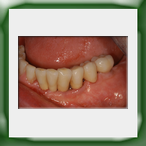

Circolare lega aurea e ceramica su impianti